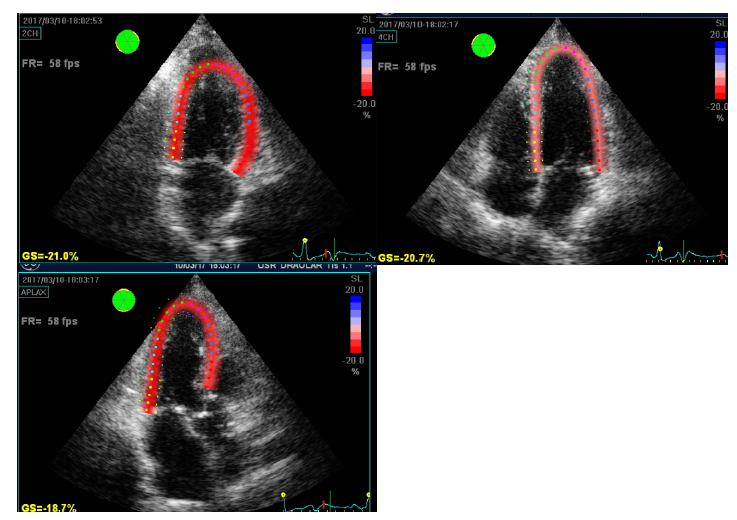

On the new echocardiogram, a 60% left ventricular ejection fraction without segmental contractility disorders was documented with an overall longitudinal strain of -21%, which is within normal limits (Figure 4). The patient is currently asymptomatic.

Figure 4 Transthoracic echocardiogram monitoring at the month of the event

The Global Longitudinal Strain (SLG) can be used to evaluate regional myocardial function and in the case of STT it has been proposed that the pattern of distribution in the acute phase affects only the apical segments, similar to the image of the evil eye ". In addition, the radial strain is reduced along the left ventricular mid-circumference as opposed to the acute myocardial infarction.17,19 In patients with the classic STT presentation, there is a decrease of the SLG from the base to the apex with a significant gradient indicating a more severe involvement of the apex, and these alterations in the regional strain improve in the early follow-up, on average at 34 days of the event.17,18,20